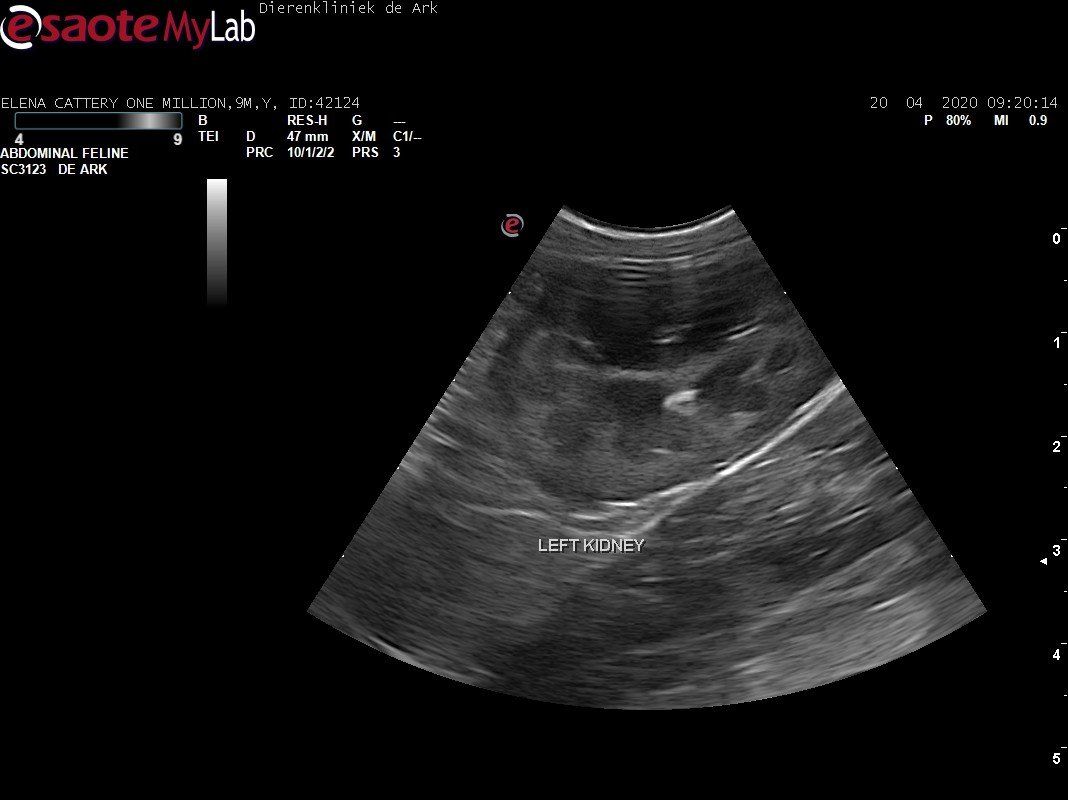

3,200 kg , echo en nieuw bloedonderzoek gedaan wat perfect ging door middel van gapabetine

Voor de garanties en om recht te hebben op medicatie bij herval eist Mutian diverse onderzoeken en controle momenten. Dit zijn bloedonderzoeken maar ook zoals hieronder te zien is echo's. Elana is volledig gecontroleerd op afwijkingen, gelukkig waren de echo's goed.

Ook de bloeduitslagen waren in orde, we kregen groen licht om te stoppen met behandelen en de wachtperiode in te gaan.